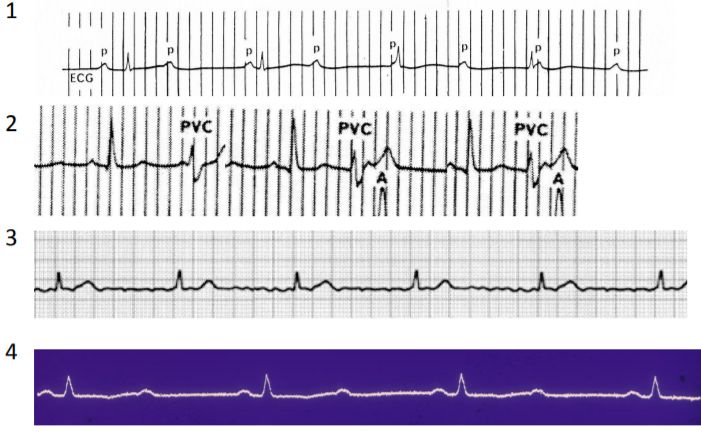

15. 50歲男性,患有糖尿病,胰臟癌及恐慌症,因突發性呼吸困難至急診求診。病患並無明顯胸痛或冒冷汗,意識清楚但情緒緊張,理學檢查發現體溫36.5℃,血壓 145/95 mmHg,脈博112/min節律規則, 呼吸 24/min快且深;四肢冰冷有輕微發紺現象。頸靜脈壓12 cm H2O,無明顯心雜音。呼吸音雙側正常,腹部平坦無壓痛,四肢活動正常亦無水腫。護理人員給予脈衝血氧定量計 (pulse oximeter) 偵測發現SpO2 84%,急診醫師隨即指示使用Venturi mask O2 35%。約半小時後,病人自覺症狀略為減緩,此時之動脈氣體分析: PH 7.50, PaO2 70mmHg, PaCO2 25 mmHg, HCO3 23 mEq/L, one touch blood glucose 320 mg/dl. EKG除竇性頻脈外其餘正常,胸部Ⅹ光如附圖,下列診斷何者最有可能? (A) Acute pulmonary embolism (B) Panic disorder related hyperventilation syndrome (C) Diabetic ketoacidosis (D) Endobronchial foreign body (E) Bronchial asthma